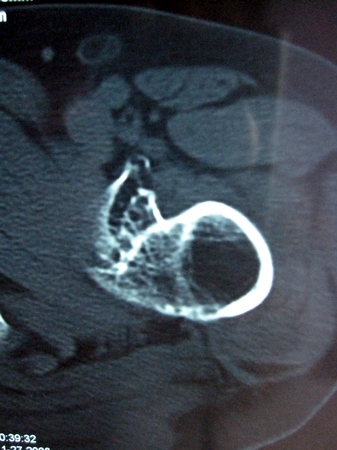

以下是引用lkc8963在2008-12-19 21:19:00的发言:[br]左?右?患侧大转子上移,股骨颈骨质浓杂,髋周见多发条片状骨化影,以小转子为著,多为陈旧性股骨颈骨折后改变并骨化性肌炎.请咨询既往史!